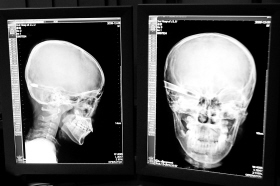

在接受x光檢查的小沖

“還是先做個X光透視,看一下箭桿到底有多深!毖劭漆t(yī)生緊急趕到CT室查看,和放射科的幾位醫(yī)生共同研究后,決定先讓小沖做X光透視。

“如果再用點力,就從后腦穿出來了!”由于小沖無法移動,醫(yī)生拿來移動插座,將透視的光板放在小沖的移動病床上,透視后讓在場的醫(yī)生都吃了一驚:箭桿直接穿過了大腦和小腦,箭尖兒直抵后顱骨,足足有10余厘米。

“從目前的情況看,必須請腦外科的專家來會診!笨催^小沖的片子,一位醫(yī)生皺緊了眉頭,神經(jīng)外科的專家問詢后也緊急趕到急診室。